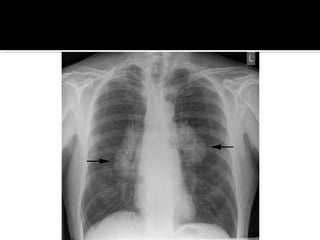

Este documento fornece parâmetros técnicos para realizar uma radiografia de tórax, incluindo posicionamento correto do paciente, dose adequada de radiação e estruturas anatômicas a serem avaliadas, como coração, pulmões, pleura, diafragma e ossos do tórax.